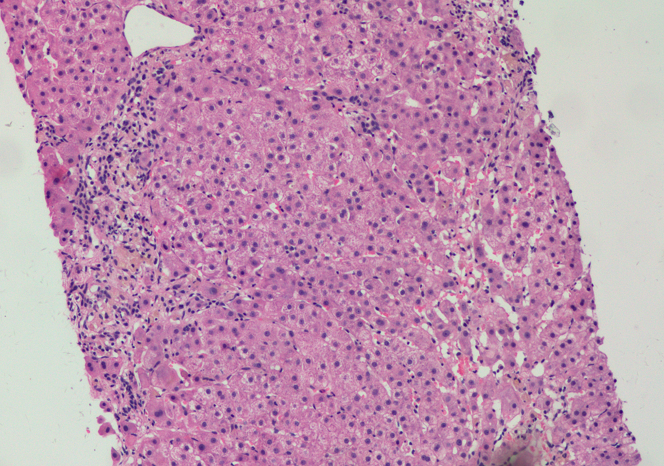

病理解读:肝细胞肝板结构基本正常,有点状坏死及炎症侵犯,病变汇管区为主,有嗜酸小体及肝细胞肿胀,肝细胞淤胆,炎症细胞以淋巴细胞多见,少量嗜酸粒,胆管增生明显,胆管破坏不明显,未见纤维化。总体印象,急性肝炎样变化。

与其他类型的病毒性肝炎相比,人类HEV感染的组织病理学的信息较少。急性戊型肝炎肝损伤的典型模式类似于其他形式的急性肝炎中发现的典型病变。包括肝细胞膨胀、凋亡(嗜酸)体散落以及汇管区淋巴细胞浸润。中性粒细胞在实质和汇管区中相对常见,这在其他类型的病毒性肝炎中少见,淋巴细胞是主要的浸润细胞类型。对HEV感染常有胆汁淤积。可以是轻度或中度的可有胆小管堵塞,并导致肝细胞肿大并呈菊团样排列,特别是在汇管区周围区域。一些临床非常明显的胆汁淤积型案例在病理学可能较少的肝细胞损伤,戊型肝炎的胆汁淤积形式可能类似于甲型肝炎病毒(HAV)感染。胆汁淤积也可见破坏性胆管炎。严重的情况下,可能存在广泛的肝细胞坏死和实质塌陷,伴有明显的导管反应。